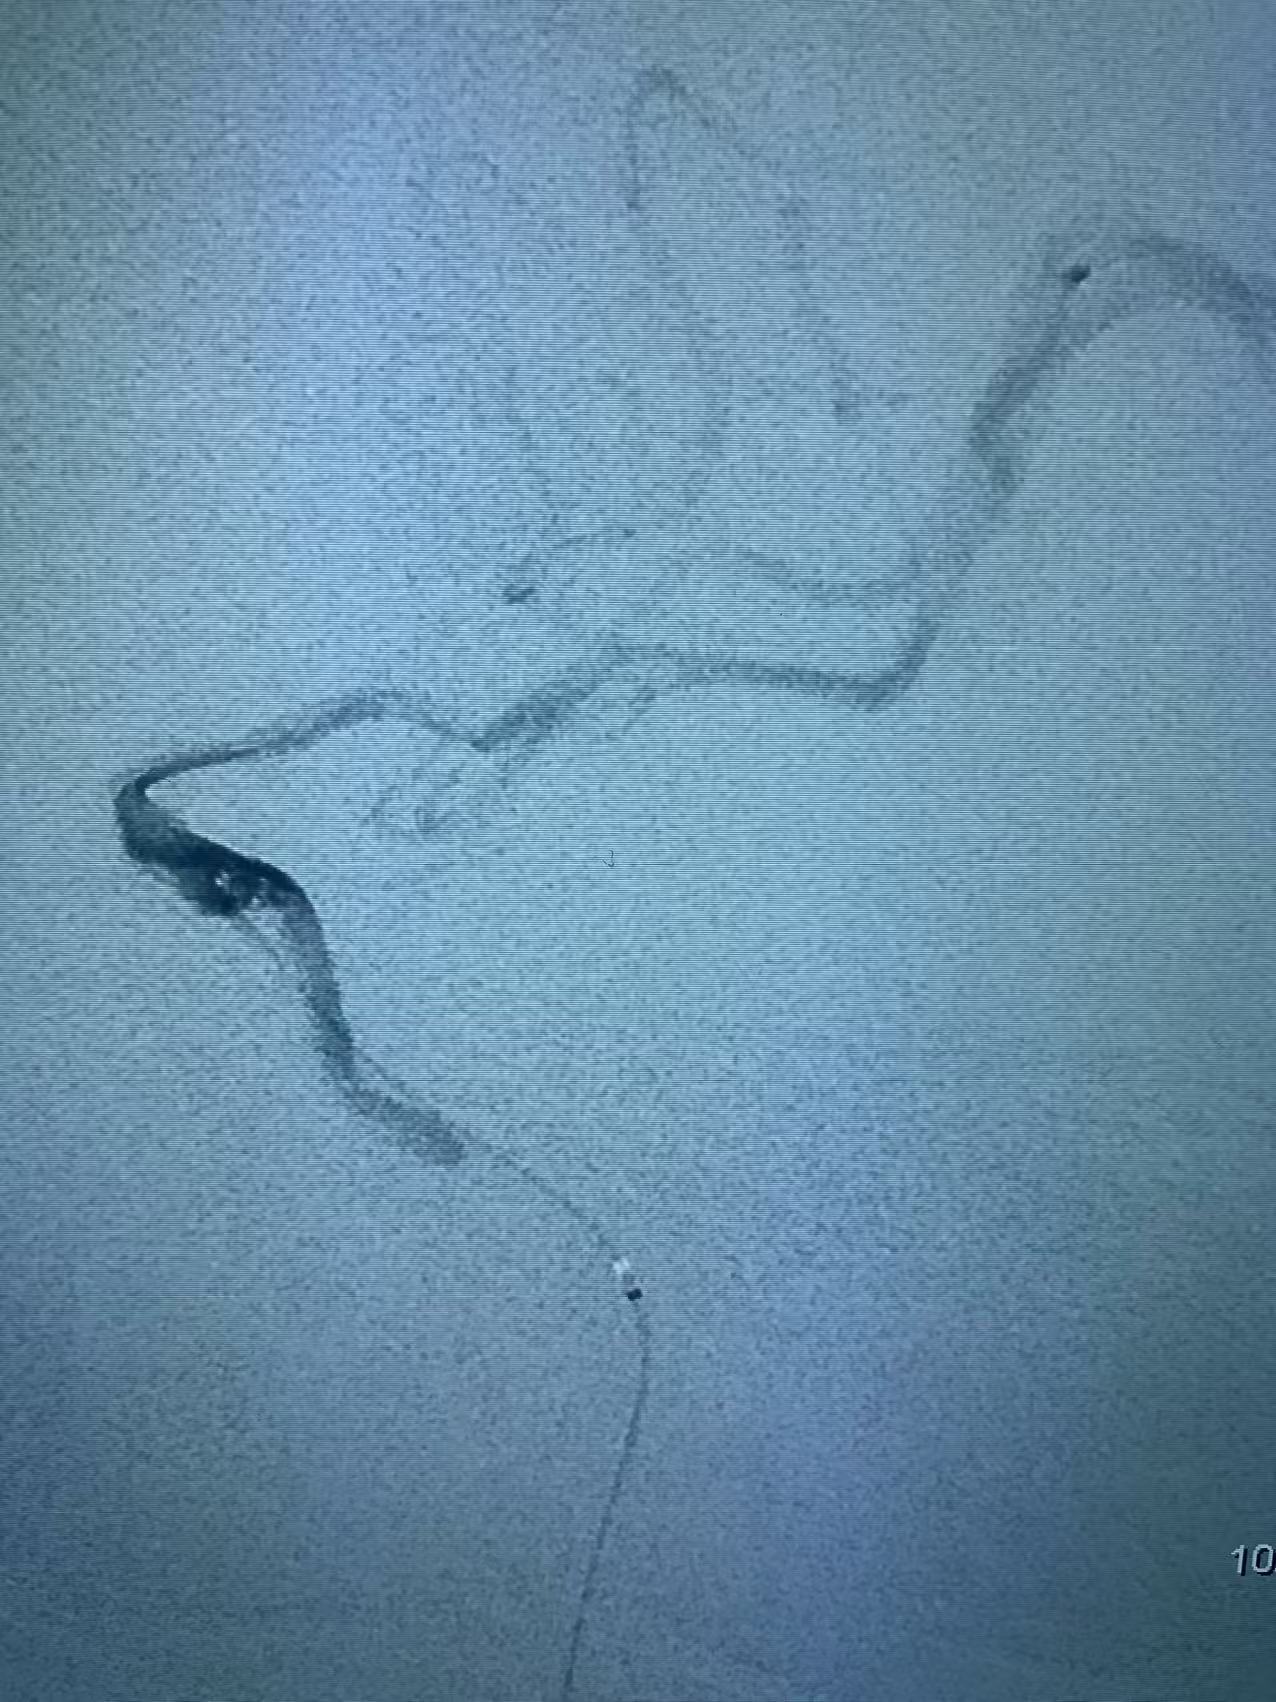

颈内动脉开口重度狭窄基础之上的急性闭塞